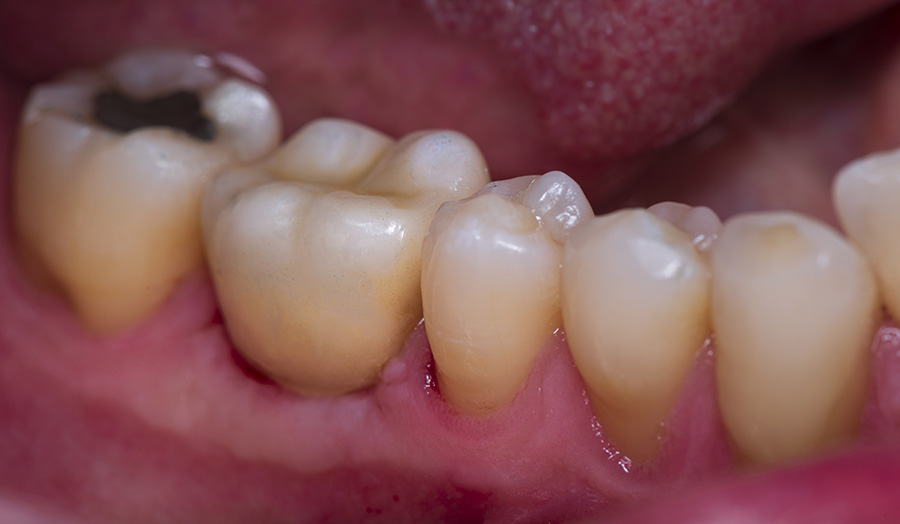

A 58-year-old male patient presented himself to my practice with a missing tooth #30 to restore the natural chewing function while preserving healthy tooth structure. The gap was to be restored with an implant and a ceramic crown. I planned and implemented the treatment digitally.

Before: Initial oral situation of missing tooth

Usage: 3D-printed surgical guide manufactured with Primeprint Guide material

After: 3D-printed temporary restoration with Primeprint Temp material (first comparison) and final restoration (second comparison)